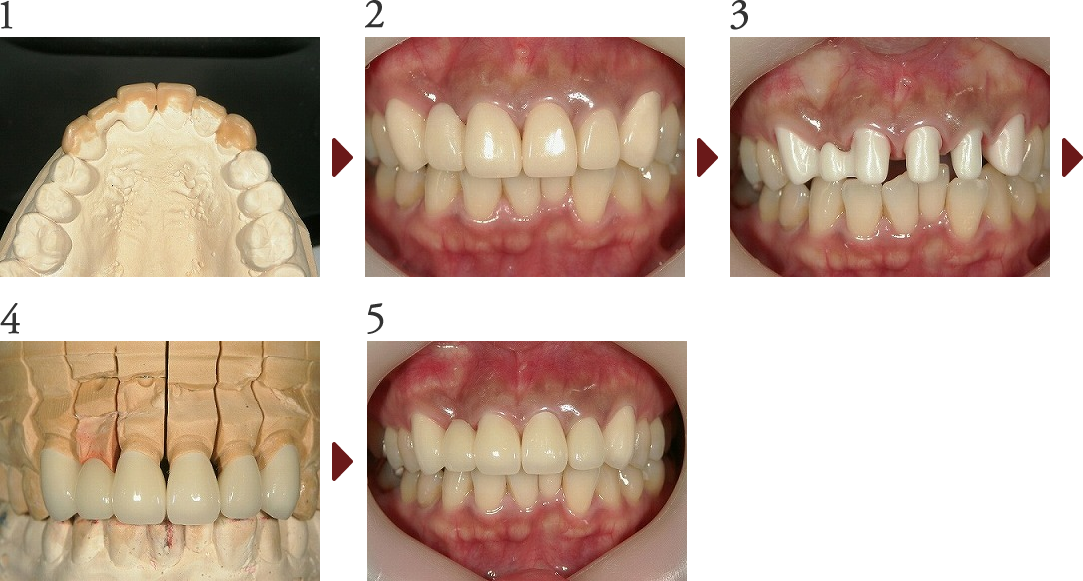

Case.1

審美修復(オールセラミックス修復)

患者さんは以前より気にされていた上顎前歯の審美的改善を目的に、オールセラミックス冠による審美修復を行う事となりました。

患者様、技工担当のテクニシャンの方と相談し、まず模型上にて診断用WAX UPを行い、プロビジョナルレストレーションを作成、口腔内で調整を繰り返し理想形を作り上げていきます。

歯の長さ、幅、傾斜角度、等々ほぼファイナルに近づいた段階で、最終プレパレーションをし、ジルコニアフレームの試適を行いセラミックスを築盛し完成させていきます。

最終的には描いていたイメージ通りに仕上がり、患者様も喜んでおられました。

(技工担当:北見市デンタルプランニング 工藤 利一氏)